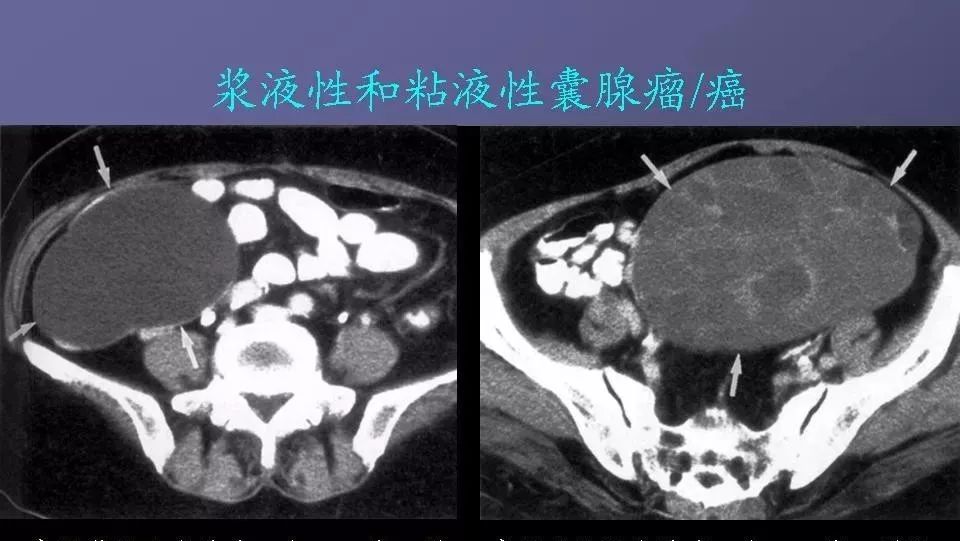

卵巢肿瘤的影像学表现及鉴别 医学界影像诊断与介入频道 · 公众号 · 医学 · 7 年前 · |